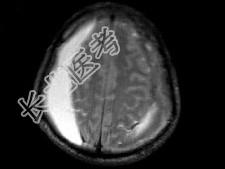

- 单项选择题男,59岁, 半月前与人打架后感头痛头昏,双侧肢体无力, 根据所提供图像,最可能的诊断是 ( )

A、双侧额顶部硬膜下血肿

B、双侧额顶部硬膜外血肿

C、双侧额顶部脑挫裂伤

D、双侧额顶部急性硬膜外血肿

E、双侧额顶部慢性硬膜外血肿